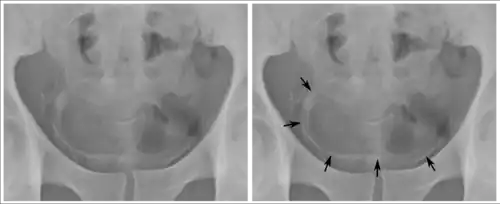

Calcifications on bladder wall caused by urinary schistosomiasis

Cystitis refers to infection or inflammation of the bladder. It commonly occurs as part of a urinary tract infection.[25] In adults, it is more common in women than men, owing to a shorter urethra. It is common in males during childhood, and in older men where an enlarged prostate may cause urinary retention.[25] Other risk factors include other causes of blockage or narrowing, such as prostate cancer or the presence of vesico-ureteric reflux; the presence of outside structures in the urinary tract, such as urinary catheters; and neurologic problems that make passing urine difficult.[25] Infections that involve the bladder can cause pain in the lower abdomen (above the pubic symphysis, so called "suprapubic" pain), particularly before and after passing urine, and a desire to pass urine frequently and with little warning (urinary urgency).[25] Infections are usually due to bacteria, of which the most common is E coli.[25]